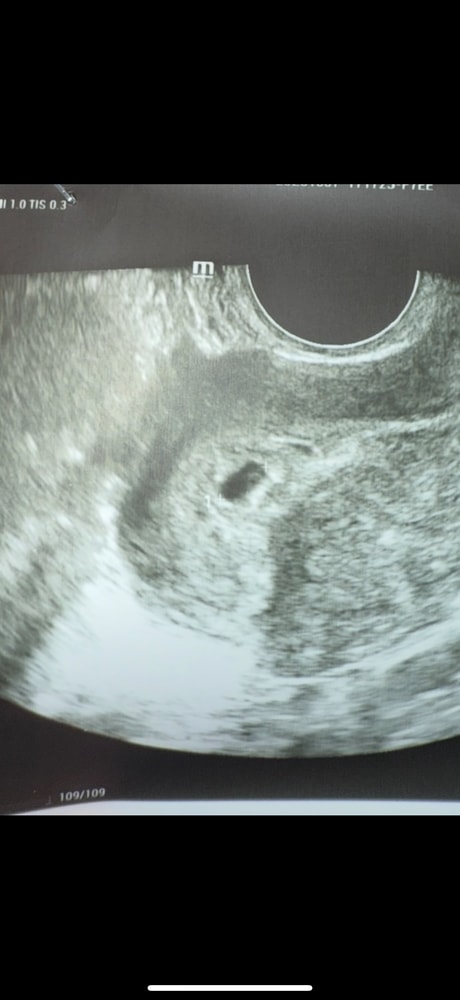

Возможна ли двойня по узи? У кого так было на ранних сроках?)

Anetta , вижу не только я, но и другой врач гинеколог, но под вопросом, говорит. Спрашиваю тут у тех, у кого, возможно, было также, чтобы послушать разные мнения.

Полина , вероятнее всего это просто тень, было у подруги такое, только там три пятна было но итог яицо было одно. Ей врачь объяснил но уже не помню как точно но смысл это тень.

Марина, возможно и тень) как раз пойду на повторное узи через недельку на СБ чтобы развеять все сомнения))

На 5 -й не увидели, на 7 были уже слышны сердца двоих

Моноамниотическая двойня Кесарево и двойня